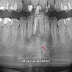

imagem : Röentgen operando uma de suas máquinas de raios -X (DOTmed News)

Em 8 de novembro de 1895, Röentgen descobriu os raios-X, assim os chamou por ainda não conhecer sua natureza.

Graças a este homem, temos as imagens radiográficas!